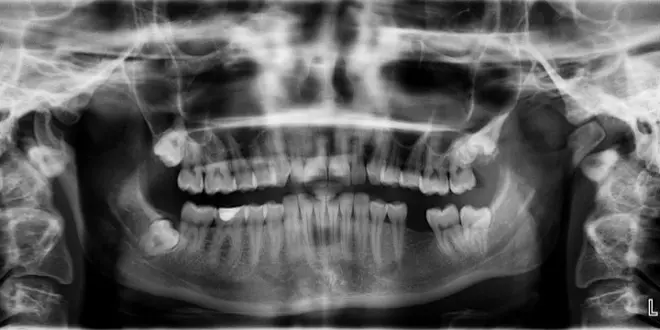

A l'hôpital, l’enfant passe plusieurs examens dont une radio de la bouche. Les médecins font alors une étonnante découverte : un sac, rempli de petites dents, a poussé sous la mâchoire. C’est cette excroissance qui a provoqué les douleurs et les gonflements.

Pour retirer toutes les dents, une intervention chirurgicale de plus de 5 heures, sous anesthésie générale, est nécessaire. C’est à ce moment-là seulement que les médecins ont pu compter le nombre exact de dents : 526 en tout allant de 0,1 millimètre à 15 millimètres. Après l’intervention, l’enfant n’avait plus que 21 dents et était en bonne santé.